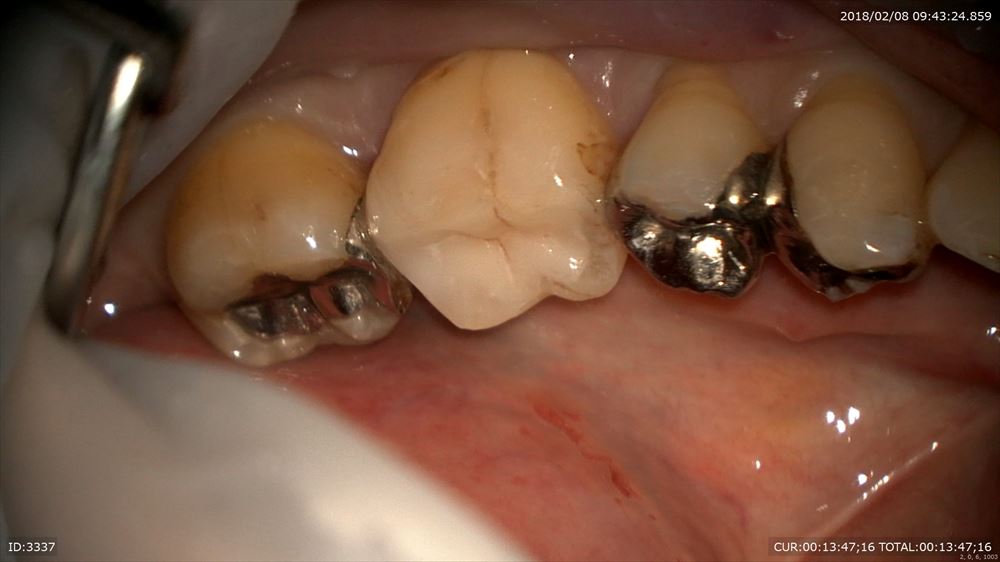

フィット

このように隙間がなく細菌の侵入を防ぎます。

とにかくやり直しのない治療を目指す為に当院では金属を使用しません。